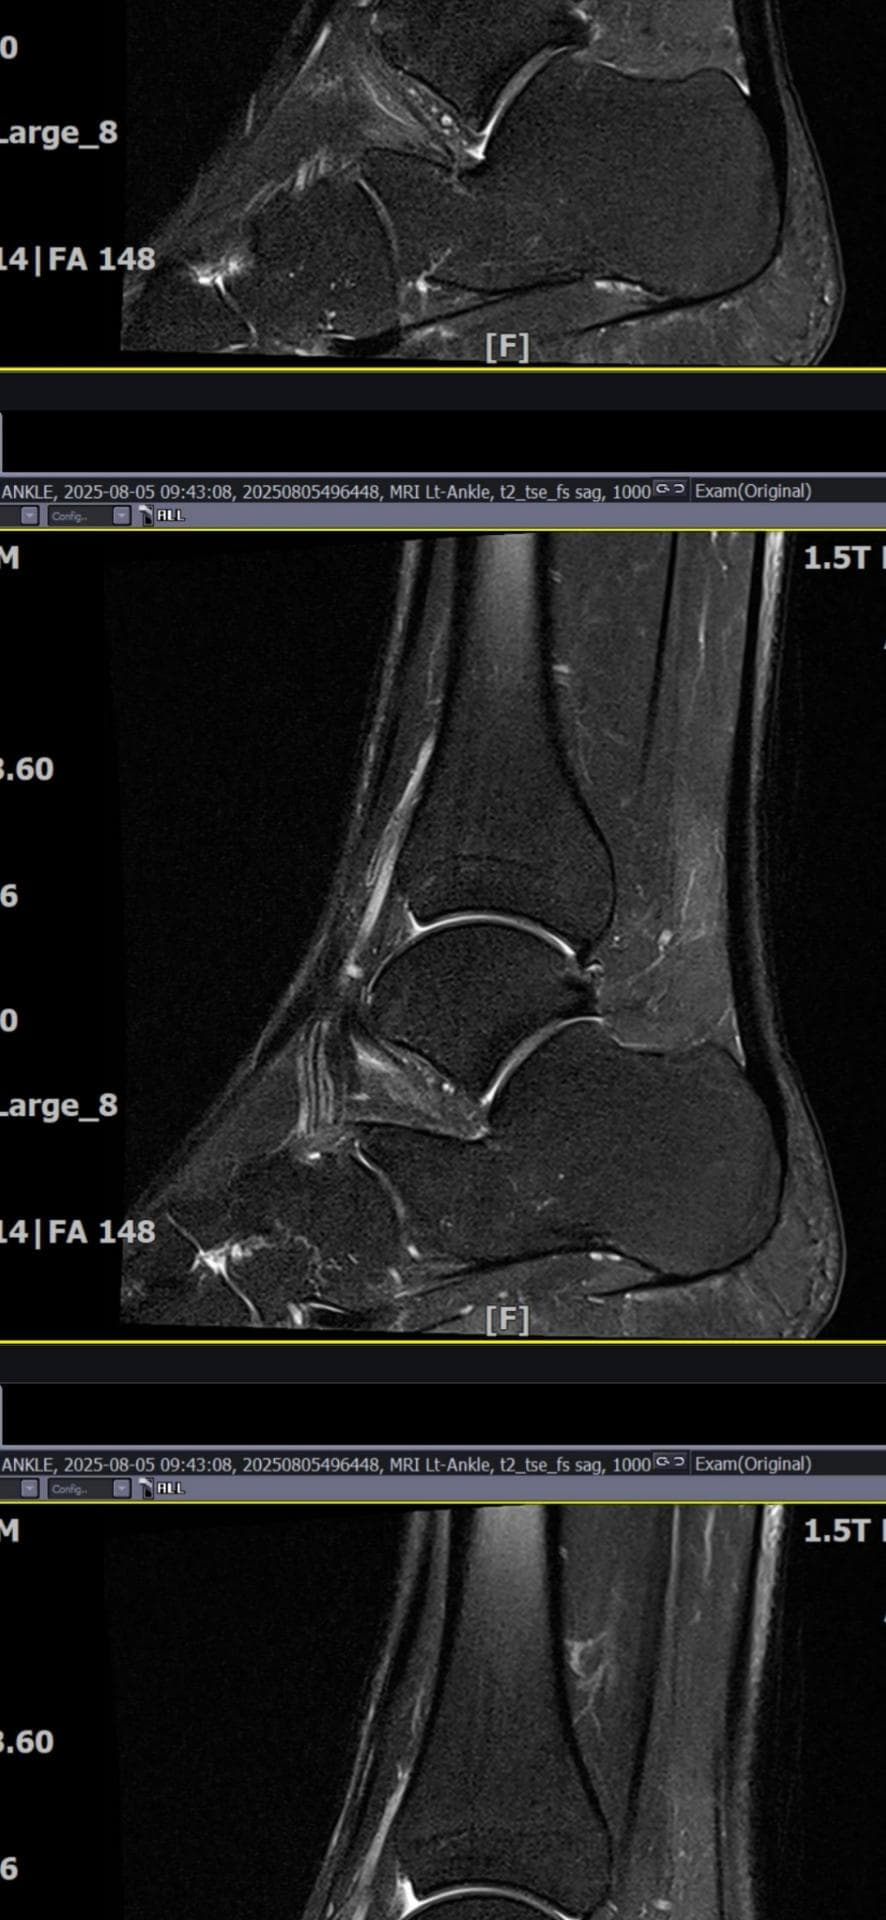

그래도 통증이 남아 8월 5일에 MRI를 촬영했는데, 병원에서는 “인대는 이어져 있고, 이 정도면 재활운동으로 호전될 것”이라는 설명을 들었습니다.

MRI 상 전거비인대와 발목 상태가 정말 회복 단계인지, 아니면 만성으로 넘어가는 건 아닌지 전문가분들의

의견을 듣고 싶습니다.

올려주신 mri를 보면 전거비인대는 연속성이 유지되고 있고 파열이나 큰 손상 흔적은 없어 재활로 회복 가능한 상태로 보입니다 다만 3개월 가까이 활동 시 통증과 미열감이 남아 있는 것은 조직 회복이 아직 완전히 끝나지 않았거나 주변 연부조직 관절 움직임 제한 등으로 인한 과민 반응일 수 있습니다.

초음파와 비교하면 mri 상으로 인대 연속성이 확인되므로 심각한 악화나 재파열은 아닌 것으로 판단됩니다

MRI상에서는 인대의 회복이 이루어지고 있는 덧으로 보이지만 인대의 회복은 소요되는 시간이 오래 걸리고, 주변 근육의 약화나 기능 저하로 인해 통증이나 불편감이 지속될 수 있습니다.